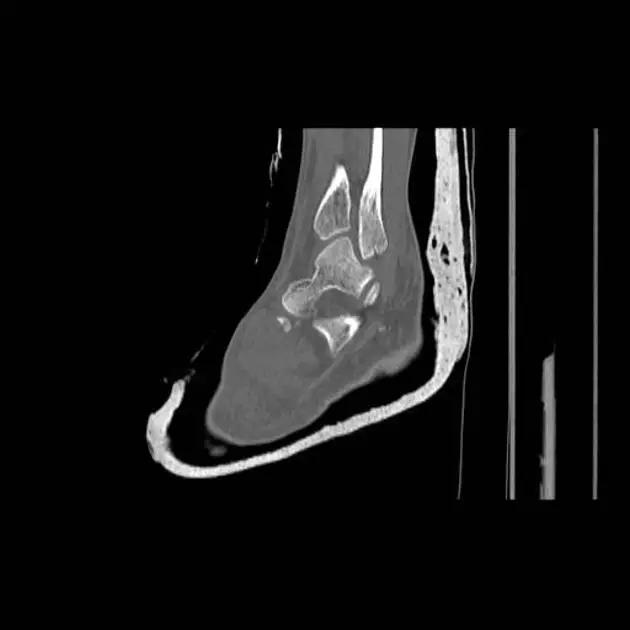

12. Cedell 骨折

距骨后内侧结节骨折。

Cedell 骨折的 CT 片 (来源:Fracture of the posterior medial tubercle of the talus :A case report and review of the literature. Acta Orthop. Belg., 2007, 73, 804-806)